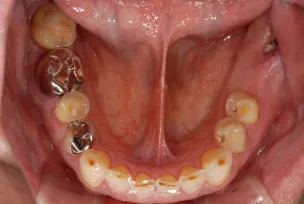

初診時

| 患者様のお悩み | 咀嚼障害(左下奥歯) |

|---|---|

| 治療法・使用素材 | 自家歯牙移植治療 |

| 患者様の年代 | 30代 |

| 治療開始年齢 | 30代 |

| 治療にかかった期間 | 6か月 |

| 性別 | 女性 |

| この治療のリスクについて | 移植歯が生着するかどうか |

| 治療にかかった費用 | 5万円 |